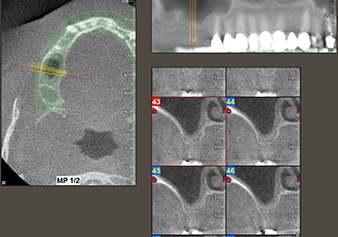

A 49-year-old female patient, a non-smoker and with nothing remarkable in her general medical history, was referred to our oral surgery practice for surgical extraction of tooth 16 and subsequent implantation. After the extraction, the patient experienced mild sinusitis trouble with the resultthat we initially waited six months before carrying out the measure. The residual bone height at the planned implant position measured 3-4 mm (Fig. 1 and 2).

The I2A instrument (diameter 2.0 mm) was then used to perforate the sinus floor intermittently and on the smallest scale possible. This special piezosurgical method ensures that the Schneiderian membrane is not damaged. When the Z25P was used, the membrane was already lifted slightly by the coolant supplied via the instrument tip (Fig. 3). The coolant quantity was just 50% in order to avoid high pressure in the implant bed.

Implant bed preparation and augmentation

Following an intermediate check (Fig. 4) a further preparation step was performed (Fig. 5). Afterwards, the hydraulic Z35P instrument was used to lift the membrane to the desired position (Fig. 6 and 7). This was followed by further piezosurgical preparation of the implant bed, concluded with a rotary bur and shoulder milling cutter up to the implant diameter of 4.8 mm. Before the implant was inserted, the augmentation material (particle size approx. 0.8-1.6 mm) was introduced underneath the Schneiderian membrane (Fig. 8).

To move the augmentation material in the direction of the maxillary sinus atraumatically, the implant was inserted very slowly by hand (Fig. 9). In the process, the membrane was pushed in the cranial direction once again. After two months, the surgical site healed without irritation. Six months later, the x-ray check showed a significant increase in opacity as an indication of ossification (Fig. 10). The prosthetic restoration was carried out with a metal-ceramic crown.